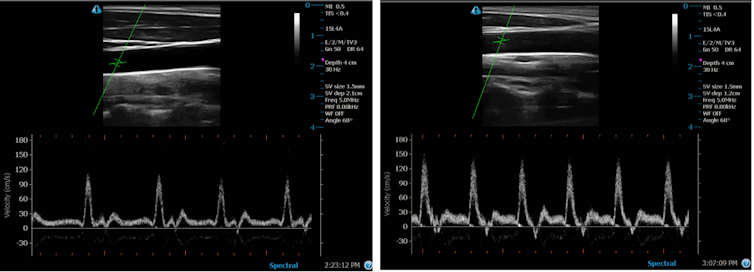

Les similitudes ne s’arrêtent pas au ressenti physique. En effectuant des échographies des artères, on observe également des augmentations similaires du flux sanguin dans les deux cas. Il est important de noter qu’en dehors de ce type de travaux de laboratoire, des études observationnelles de long terme ont révélé que l’application de chaleur au repos (ce que les universitaires appellent « chauffage passif ») constitue un moyen plaisant, pratique et efficace d’améliorer notre santé.

Lorsque notre température corporelle commence à augmenter, notre organisme doit trouver un moyen de dissiper l’excès de chaleur. L’augmentation du flux sanguin vers la peau est l’un des principaux mécanismes mis en œuvre pour y parvenir. Celle-ci résulte en partie de la vasodilatation (élargissement) des artères et des capillaires. L’élévation du flux sanguin, que je mesure dans mon laboratoire grâce à l’échographie, favorise également la production et la libération dans le sang de diverses molécules qui participent à la croissance cellulaire, à la réparation et à la protection des vaisseaux sanguins.